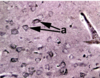

Is the cerebral cortex grey matter or white matter? Identify the structures arrowed at (a) and (b).

The cerebral cortex is gray matter.As it is the outer surface of the brain.

A-Cell body

B-Dendrites